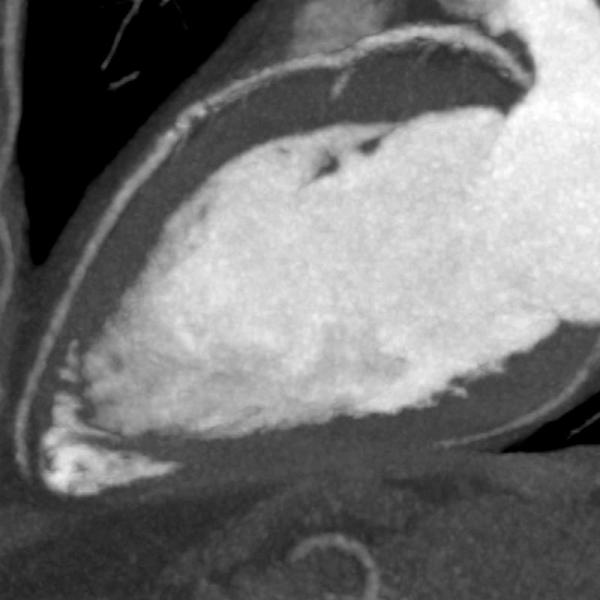

View Calcium Score 0 Ct Scan PNG. Because a computed tomography (ct) scanner is used to detect what is a coronary calcium score test? Specifically, it looks for calcium deposits in the coronary arteries that can narrow arteries and increase the risk of heart attack.

This suggests that cad is absent or so minimal it cannot be seen by this technique. A sophisticated computer program, guided by the. Specifically, it looks for calcium deposits in the coronary arteries that can narrow arteries and increase the risk of heart attack.

A ct calcium score exam, also known as a coronary calcium scan, is a quick, convenient and noninvasive way of evaluating the amount of calcified (hard) plaque in your heart vessels.

Learn more from cleveland clinic about the procedure. A negative cardiac ct scan for calcium scoring shows no calcification within the coronary arteries. A coronary ct calcium scan is a computed tomography (ct) scan of the heart for the assessment of severity of coronary artery disease. Learn more from cleveland clinic about the procedure.